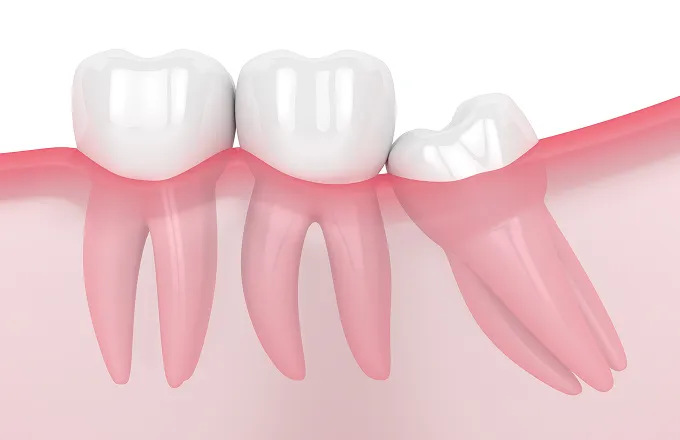

斜め/横向きに生えている

親知らず抜歯

斜め/横向きに生えている親知らずイメージ

費用(1本) 約1,500〜4,000円

抜歯時間 約5〜15分